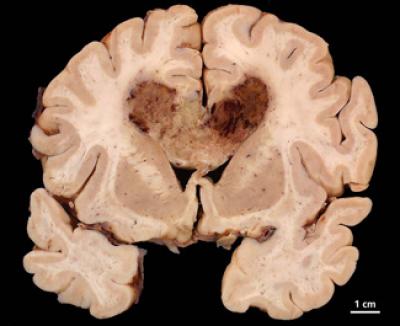

Mischel and colleagues, including Webster K. Cavenee, PhD, and Frank B. Furnari, PhD, of the Ludwig Institute and the UC San Diego School of Medicine, investigated the behavior of glioblastoma multiforme (GBM), the most common malignant primary brain cancer in adults. More than 9,000 new cases of the disease are diagnosed each year in the United States and effective treatments are limited. The tumors are aggressive and resistant to current therapies, such as surgery, radiation and chemotherapy. The median survival rate for newly diagnosed GBM patients is just 14 months.

GBM is characterized by a mutated variant of the epidermal growth factor receptor known as EGFRvIII that is found on extrachromosomal DNA in cancer cells. EGFRvIII promotes tumor growth. Some new drugs kill cancer cells by specifically suppressing or inhibiting EGFRvIII, but lose effectiveness as drug resistance soon develops.

The researchers found that this resistance may be due to the cancer cells temporarily dumping their extrachromosomal EGFRvIII, which essentially renders them invisible to drugs looking for that particular mutation. When the drug therapy is halted, the EGFRvIII reappears at previous levels and accelerated tumor growth resumes.